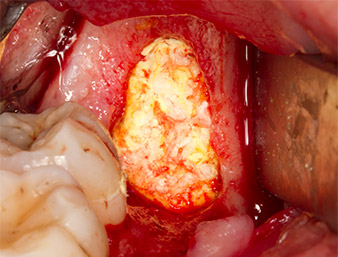

The tissue above the root remnant was not completely ossified and consisted for the most part of granulation tissue modified by inflammation (Fig. 4).

To obtain autogenous material for subsequent wound treatment, healthy bone chips were harvested from the surroundings of the root remnant with a piezo surgical instrument (Piezomed B5) (Fig. 5).